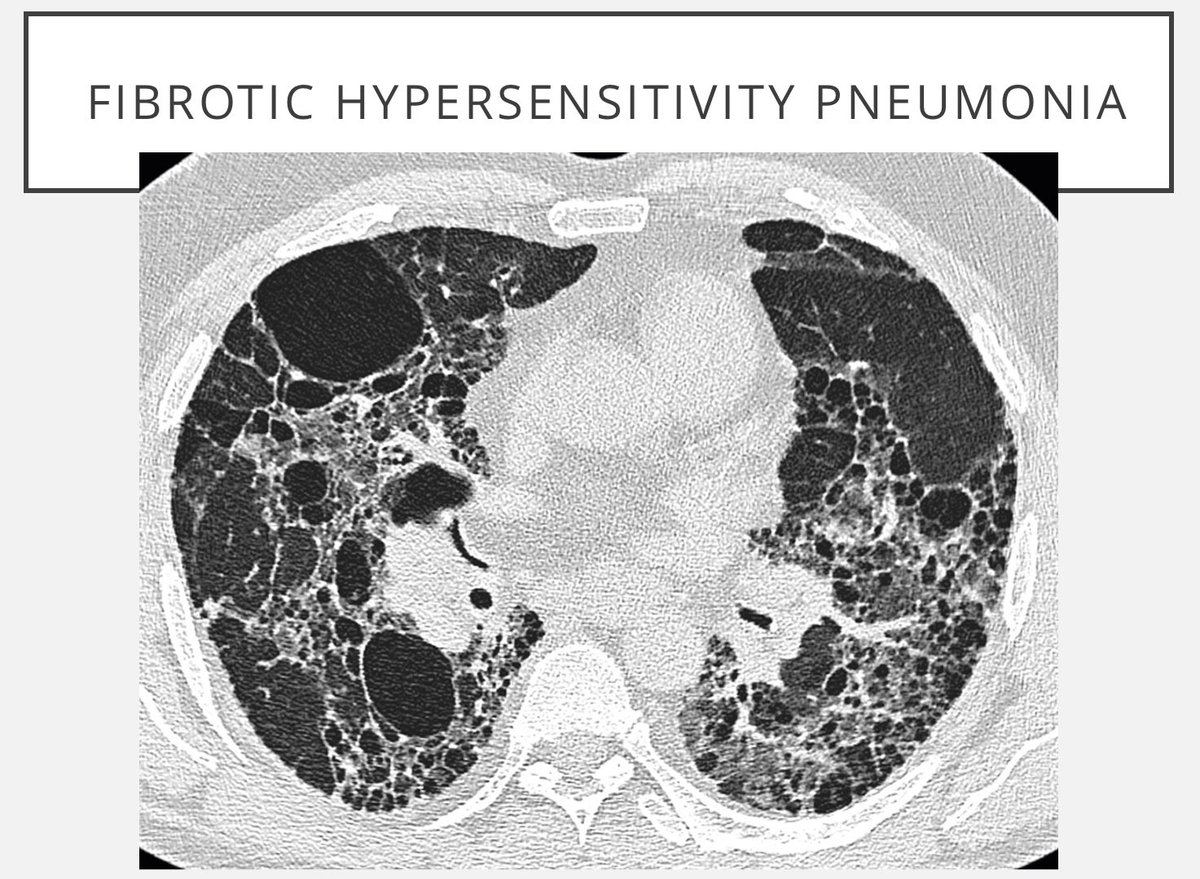

Differential Diagnosis Of Cystic Lung Are Many And Inconsistent

Cystic Lung Disease CancerGO

REF Cafe Roentgen Thoracic Thursday Lecture VII 10th Aug 2023